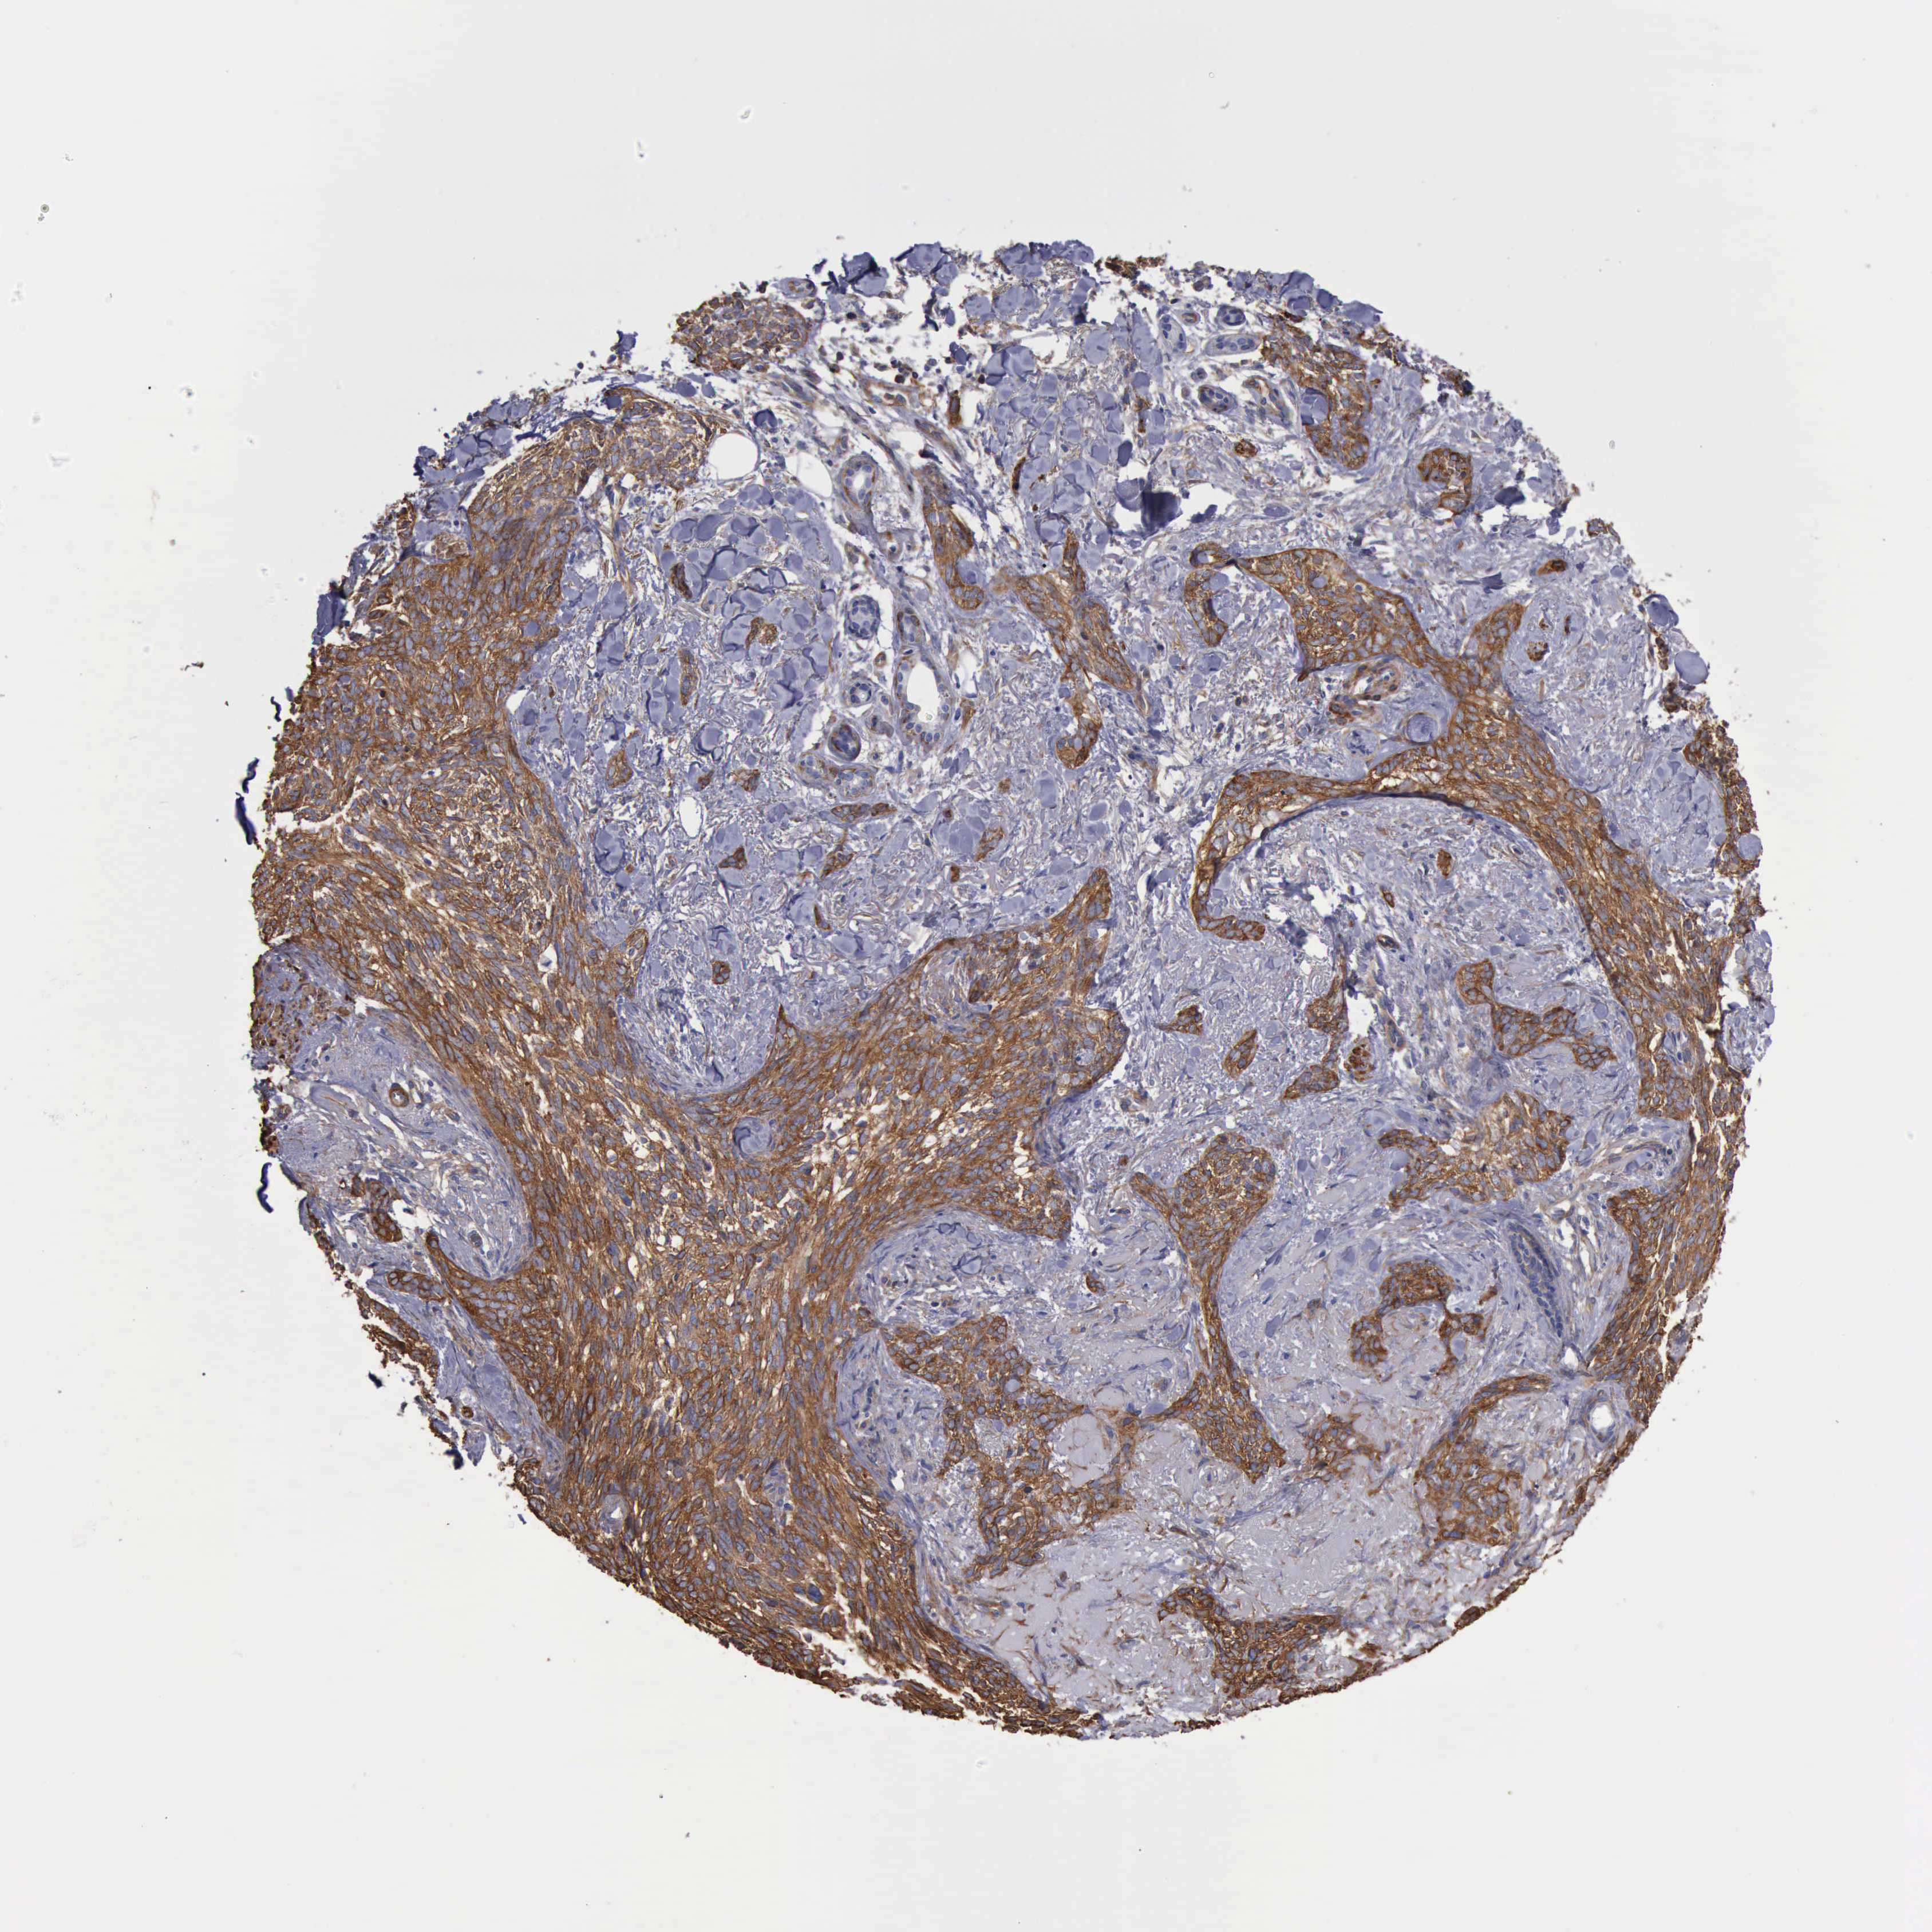

SKIN CANCER - Protein expressioni

A mouse-over function shows sample information and annotation data. Click on an image to view it in a full screen mode. Samples can be filtered based on level of antibody staining by selecting one or several of the following categories: high, medium, low and not detected. The assay and annotation is described here.

Antibody stainingi

Antibody staining in the annotated cell types in the current human tissue is reported as not detected, low, medium, or high, based on conventional immunohistochemistry profiling in selected tissues. This score is based on the combination of the staining intensity and fraction of stained cells.

Each image is clickable and will lead to virtual microscopy that enables deeper exploration of all samples and also displays staining intensity scores, fraction scores and subcellular localization as well as patient and tissue information for each sample.

Antibody HPA001115

Antibody HPA002925

Antibody CAB000356

Staining

High

Medium

Low

Not detected

Intensity

Strong

Moderate

Weak

Negative

Quantity

>75%

75%-25%

<25%

None

Location

Nuclear

Cytoplasmic/membranous

Cytoplasmic/membranous,nuclear

Squamous cell carcinoma, NOS

Basal cell carcinoma